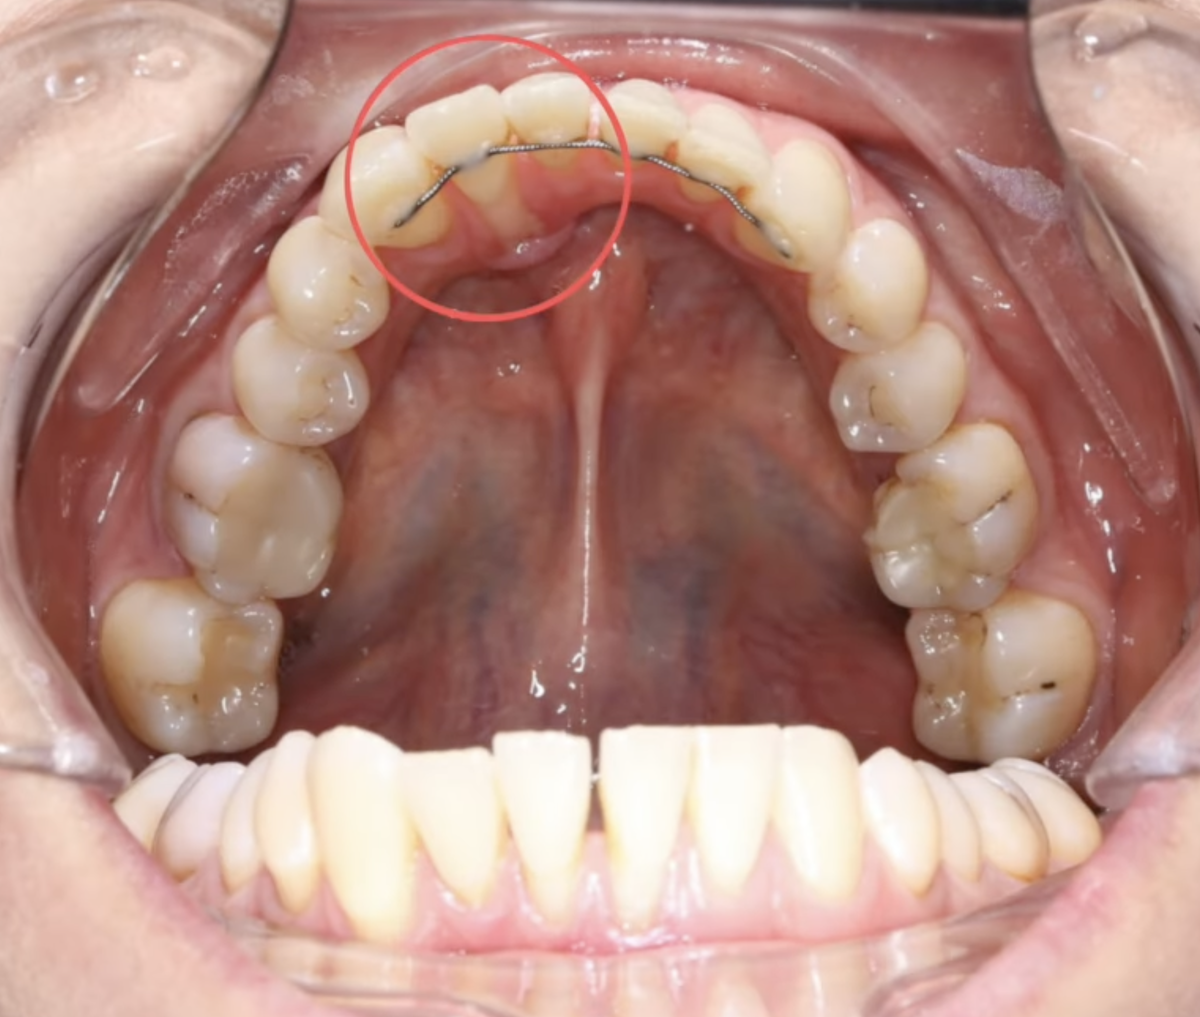

К нам в клинику обратилась пациентка за повторным ортодонтическим лечением. Ранее она уже проходила лечение.

Обратите внимание на нижнюю челюсть.

Зуб №42 — с язычной стороны мы видим достаточно сильное оголение корня.